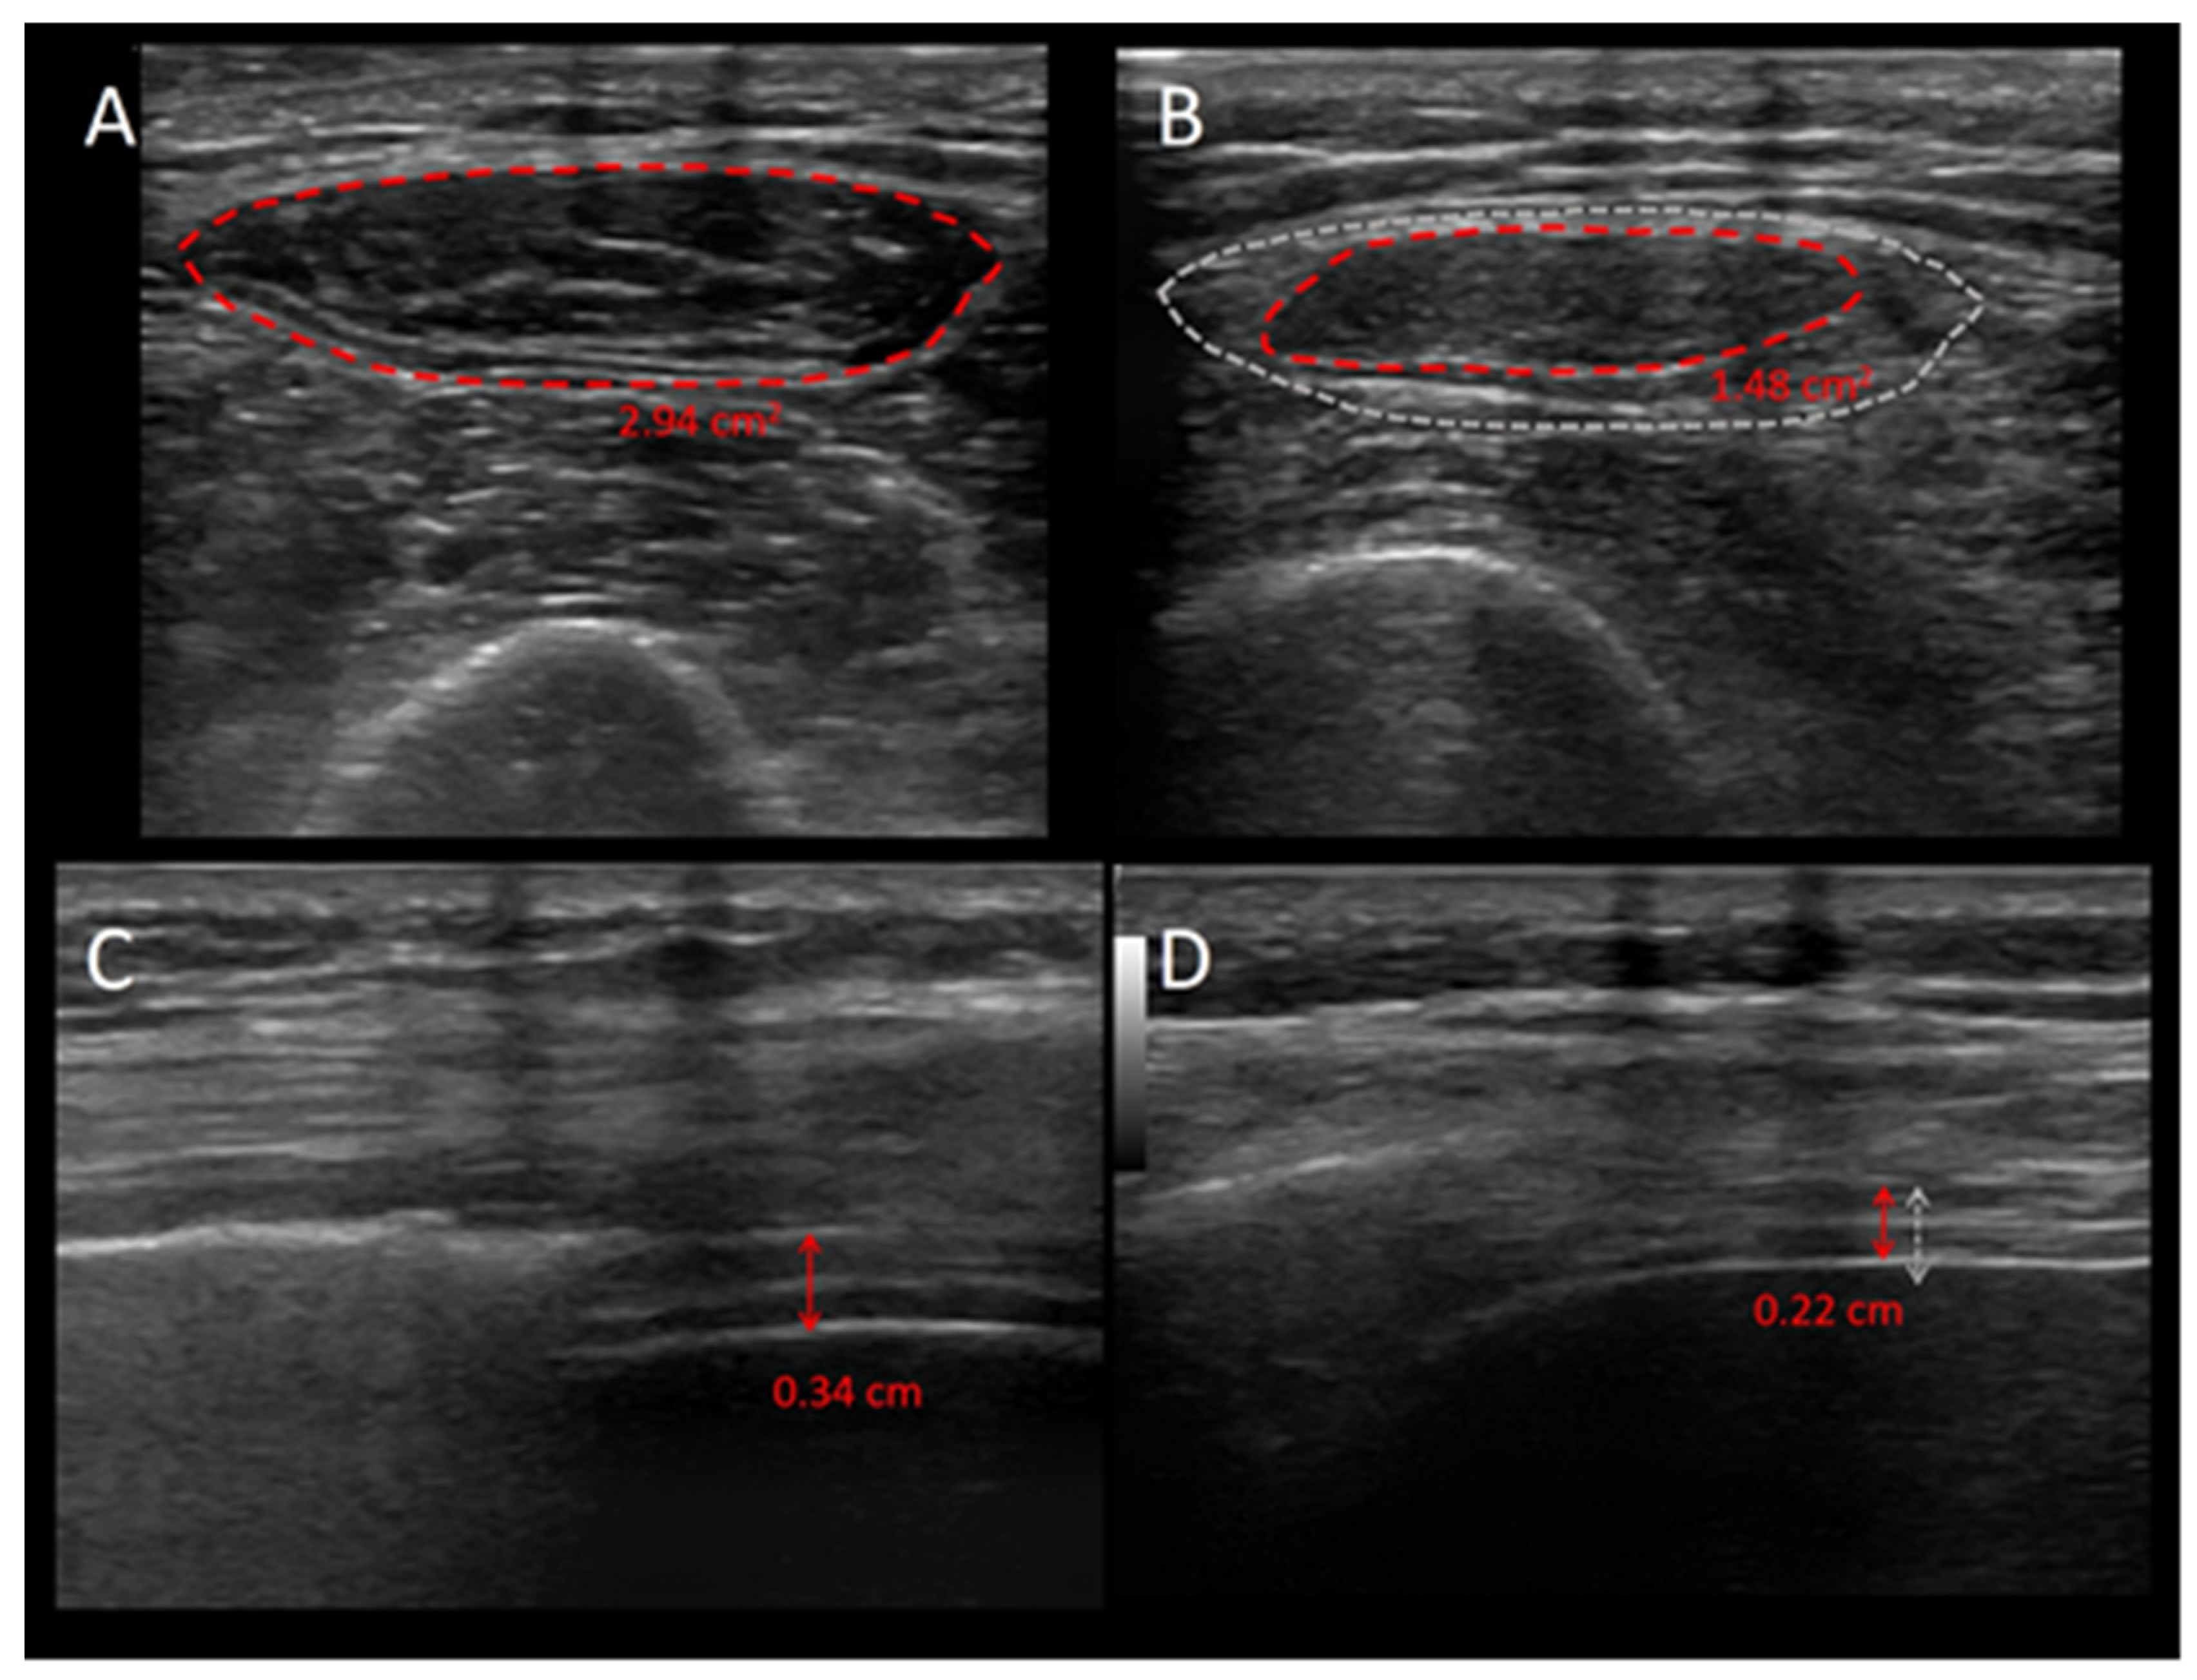

- Formenti, P.; Umbrello, M.; Coppola, S.; Froio, S.; Chiumello, D. Clinical review: Peripheral muscular ultrasound in the ICU. Ann. Intensive Care 2019, 9, 57. [Google Scholar] [CrossRef]

- Puthucheary, Z.A.; Phadke, R.; Rawal, J.; McPhail, M.J.W.; Sidhu, P.S.; Rowlerson, A.; Moxham, J.; Harridge, S.; Hart, N.; Montgomery, H.E. Qualitative Ultrasound in Acute Critical Illness Muscle Wasting. Crit. Care Med. 2015, 43, 1603–1611. [Google Scholar] [CrossRef]

- Umbrello, M.; Guglielmetti, L.; Formenti, P.; Antonucci, E.; Cereghini, S.; Filardo, C.; Montanari, G.; Muttini, S. Qualitative quantitative muscle ultrasound changes in patients with COVID-19-related ARDS. Nutrition 2021, 91–92, 111449. [Google Scholar] [CrossRef] [PubMed]

- Parry, S.M.; El-Ansary, D.; Cartwright, M.S.; Sarwal, A.; Berney, S.; Koopman, R.; Annoni, R.; Puthucheary, Z.; Gordon, I.R.; Morris, P.E.; et al. Ultrasonography in the intensive care setting can be used to detect changes in the quality and quantity of muscle and is related to muscle strength and function. J. Crit. Care. 2015, 30, e9–e14. [Google Scholar] [CrossRef]

- Formenti, P.; Umbrello, M.; Castagna, V.; Cenci, S.; Bichi, F.; Pozzi, T.; Bonifazi, M.; Coppola, S.; Chiumello, D. Respiratory and peripheral muscular ultrasound characteristics in ICU COVID-19 ARDS patients. J. Crit. Care 2022, 67, 14–20. [Google Scholar] [CrossRef] [PubMed]